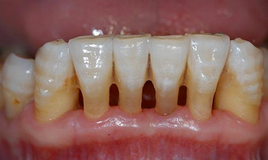

牙龈退缩,引起牙槽骨的吸收退化,最后引起牙齿松动。 其次,是受到外力的机器碰撞或咬硬的东西引起的牙齿松动。

牙齿松动的严重结果是牙齿脱落了。出现了牙周炎并且已经导致牙齿松动有什么好的治疗方法呢?

2、牙周治疗

牙周发炎引起的牙齿松动应及早就诊,可以到专业的口腔医院通过洗牙,减轻齿牙周边的炎症发生和加重,缓和牙槽骨被吸收,但需要重复多次。